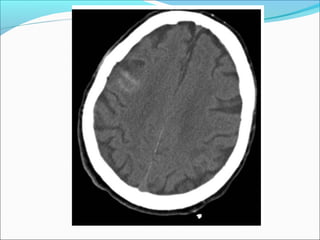

SUBDURAL HEMATOMA

Radiological signs

ļ‚—Crescent shape

ļ‚—The most common locations are the frontal and

parietal convexities.

ļ‚—Countercoup

ļ‚—Unlike an EDH, its spread is not limited by suture

lines; it can spread over the whole convexity, but it

almost never crosses the midline

ļ‚—Mass effect +/-brain herniation

ļ‚—Skull fracture in < 50 %